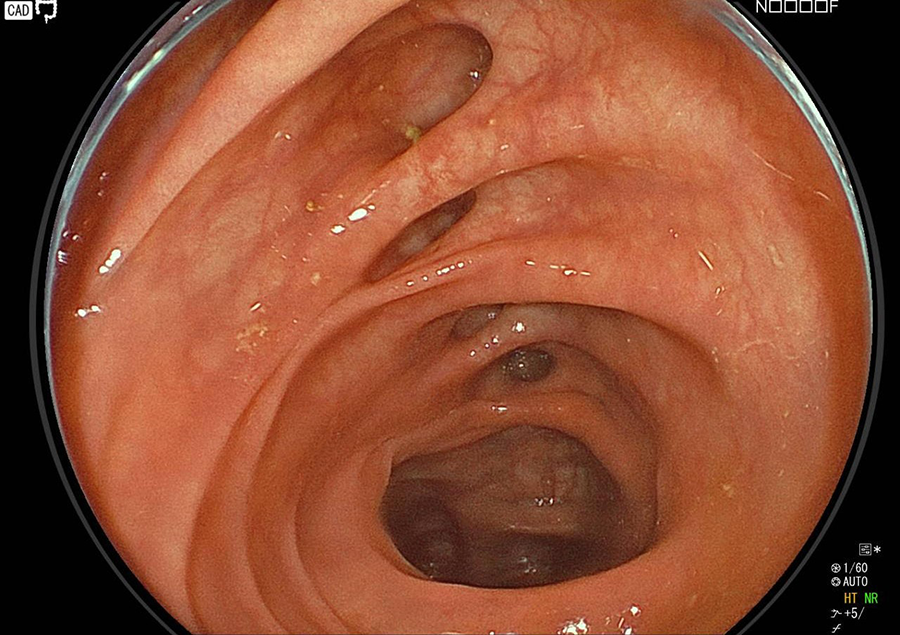

大腸カメラ検査では、肛門から内視鏡を挿入し、大腸、小腸の一部(回腸)を観察します。

検査の様子